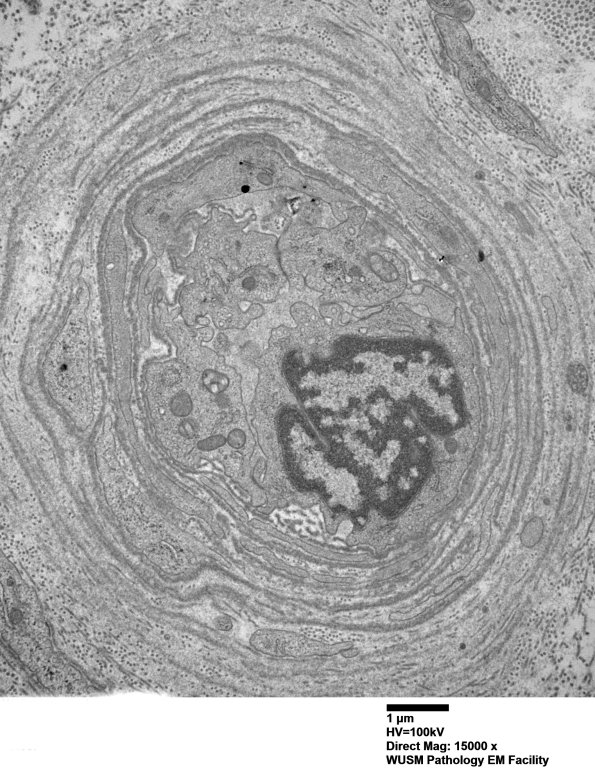

Washington University Experience | VASCULAR | Hypoxia-Ischemia, fetal-neonatal | White Matter | 13C1 (Case 13) EM022 - Copy

13C1 (Case 13) EM022 - Copy